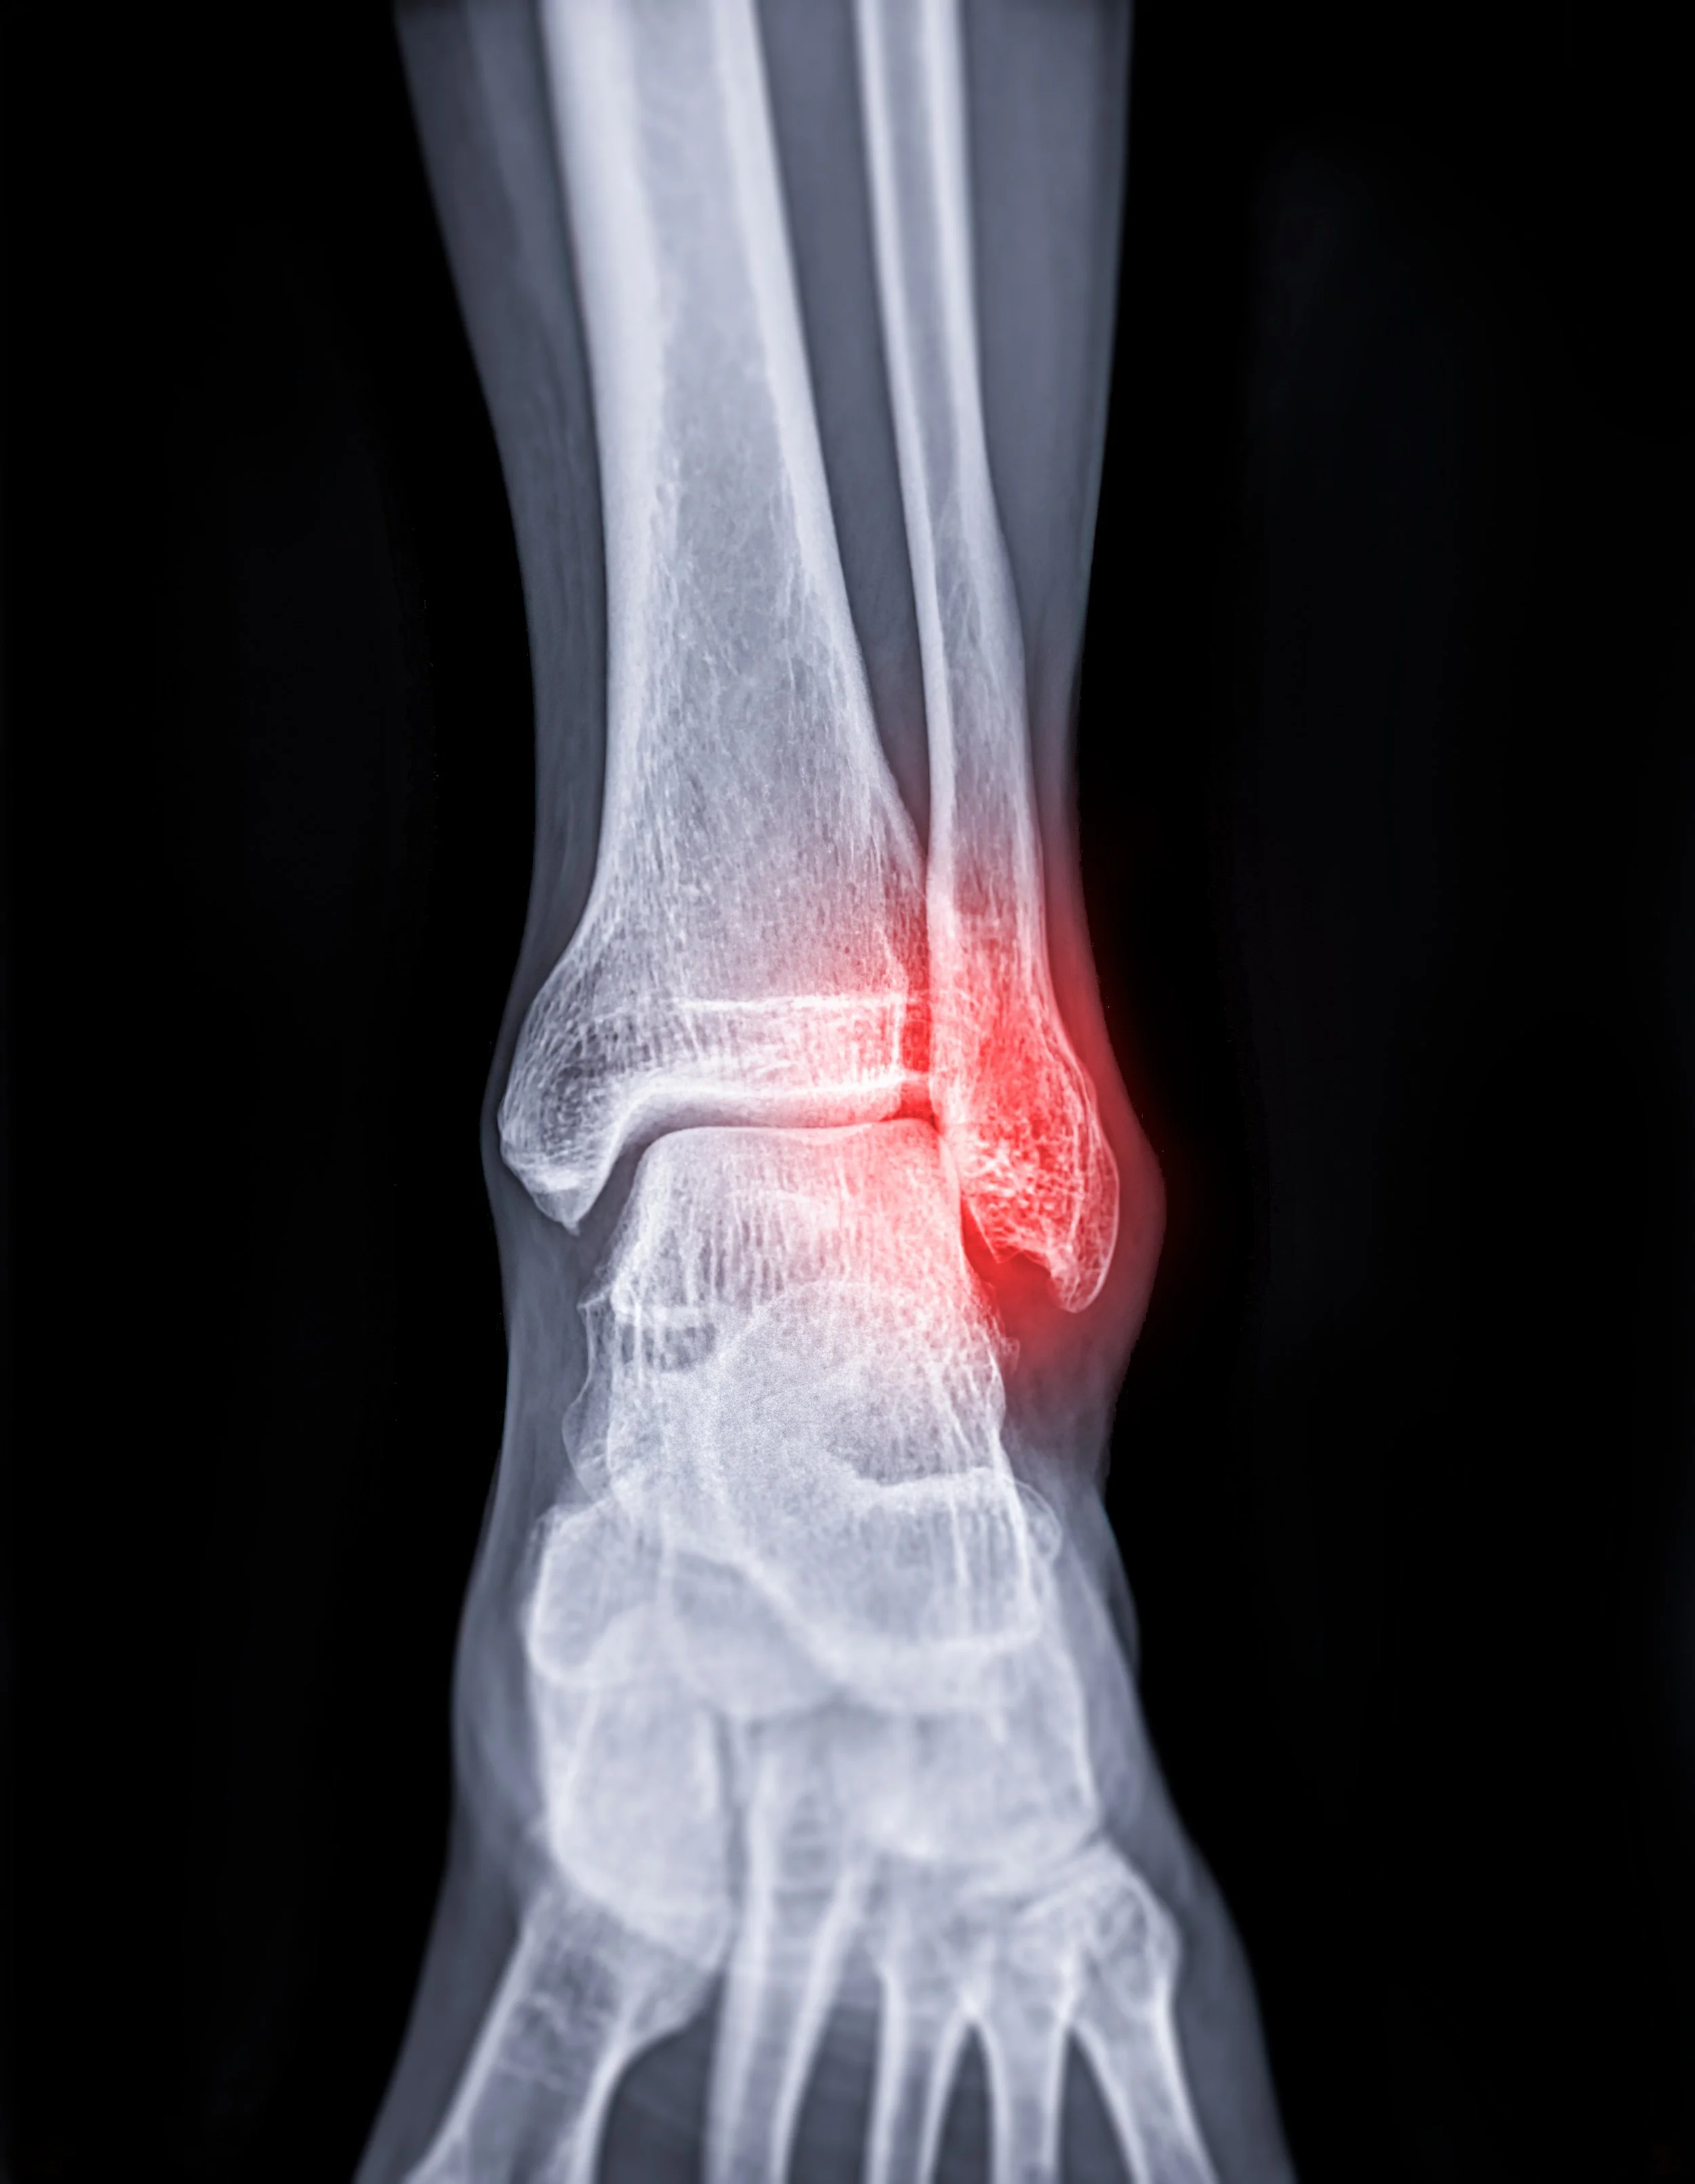

X-ray image of ankle joint showing fracture of ankle joint